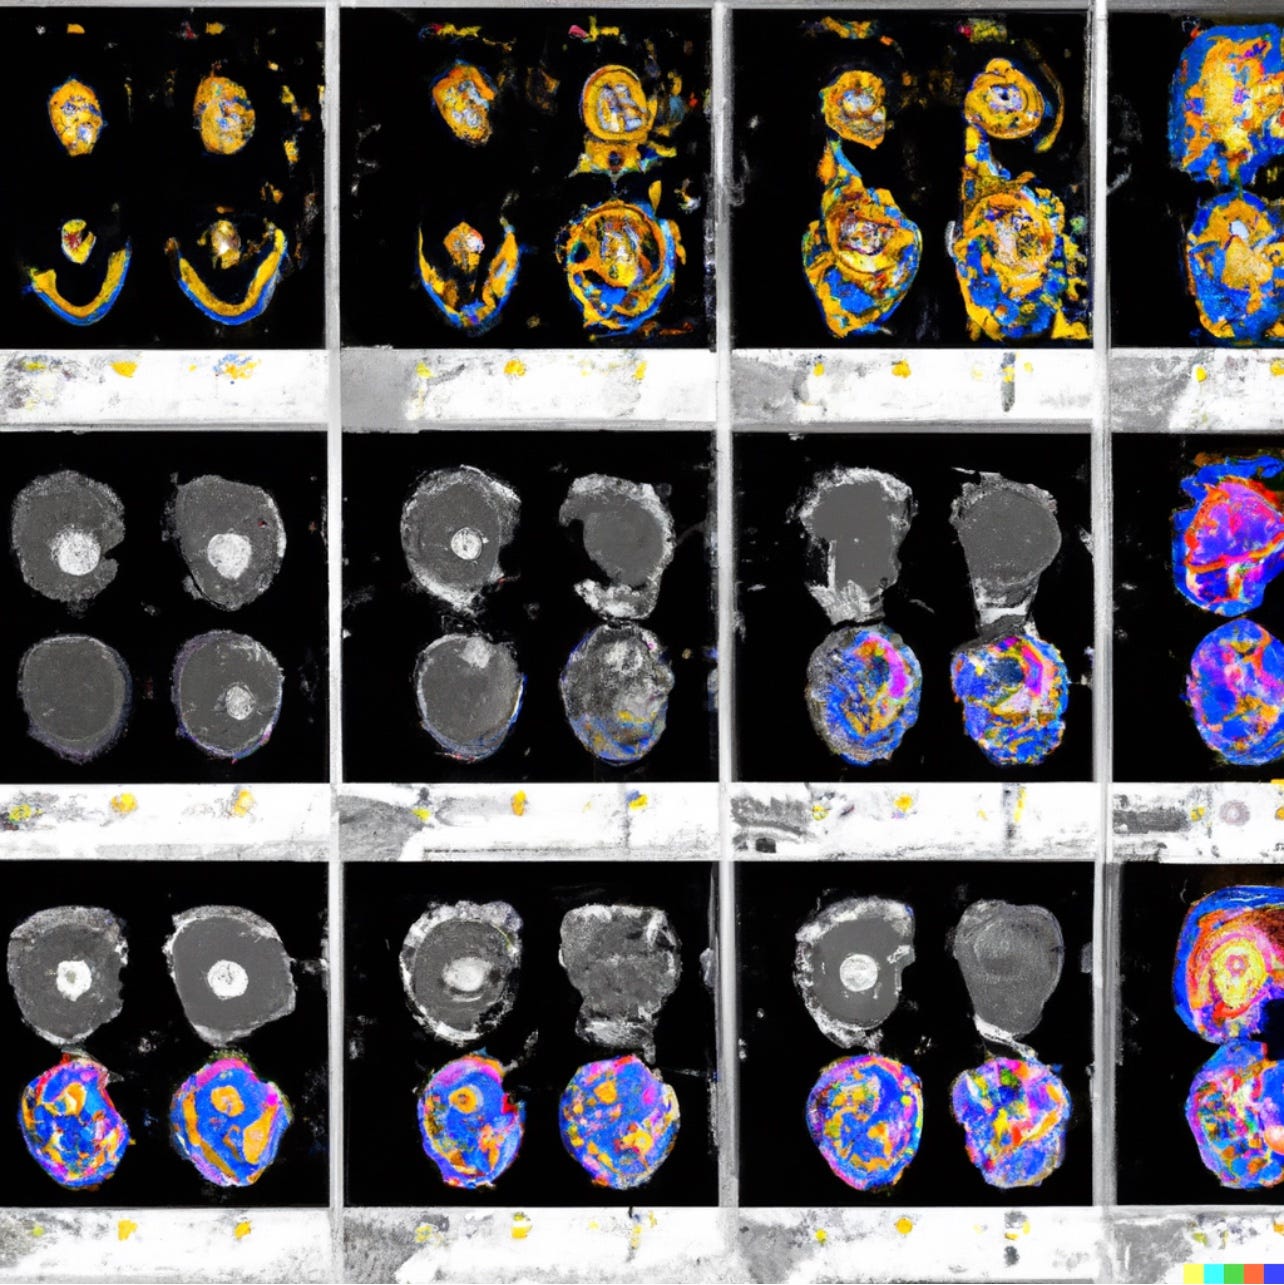

Understanding coordinate systems and DICOM for deep learning cheap, DICOM Imaging Router An Open Deep Learning Framework for cheap, Processing Computer Tomography CT for Deep Learning Applications cheap, Dicom Deep Learning 2024 www.chop rite cheap, Dicom Deep Learning 2024 www.chop rite cheap, Annotate DICOM images and build an ML model using the MONAI cheap, A DICOM Framework for Machine Learning and Processing Pipelines cheap, 4 tips on DICOM handling in Machine Learning for Healthcare cheap, Architecture of the web viewer for WSI images in DICOM format with cheap, Dicom Deep Learning 2024 www.chop rite cheap, DICOM Latest Advances in AI ML Applied to Medical Imaging cheap, Schematic of data flow for deep learning framework operation cheap, Dicom Deep Learning 2024 www.chop rite cheap, Medical Image Segmentation A Complete Guide Encord cheap, Deep Learning driven classification of external DICOM studies for cheap, Dicom Systems De identifies 5.3 Million Radiology Exams cheap, Three dimensional deep learning to automatically generate cranial cheap, Deep learning assesses additional radiation dose in overscanning cheap, Medical Image Analysis with Deep Learning Part 4 KDnuggets cheap, GitHub ben heil DICOM CNN Convolutional neural network solution cheap, Transfer Learning for Dicom Image Classification cheap, Encoding of machine learning model outputs in DICOM. A Information cheap, Introduction to 3D medical imaging for machine learning cheap, Dicom Deep Learning 2024 www.chop rite cheap, Diagnostics Free Full Text Deep Semi Supervised Algorithm for cheap, TWIMLfest Fundamentals of Medical Image Processing for Deep Learning cheap, Free software for deep learning medical image annotation cheap, A Machine Learning method for relabeling arbitrary DICOM structure cheap, Building Scalable Machine Learning Pipelines for Multimodal Health cheap, 10 Best DICOM Viewers for Medical Images 2023 Update cheap, GitHub Mattobad Pneumonia Detection Deep Learning Applying deep cheap, Deep learning in medical imaging 3D medical image segmentation cheap, Processing medical images data files for deep learning cheap, Lung Cancer Detection and Classification on DICOM Dataset cheap, Dicom Deep Learning 2024 www.chop rite cheap.

Understanding coordinate systems and DICOM for deep learning cheap, DICOM Imaging Router An Open Deep Learning Framework for cheap, Processing Computer Tomography CT for Deep Learning Applications cheap, Dicom Deep Learning 2024 www.chop rite cheap, Dicom Deep Learning 2024 www.chop rite cheap, Annotate DICOM images and build an ML model using the MONAI cheap, A DICOM Framework for Machine Learning and Processing Pipelines cheap, 4 tips on DICOM handling in Machine Learning for Healthcare cheap, Architecture of the web viewer for WSI images in DICOM format with cheap, Dicom Deep Learning 2024 www.chop rite cheap, DICOM Latest Advances in AI ML Applied to Medical Imaging cheap, Schematic of data flow for deep learning framework operation cheap, Dicom Deep Learning 2024 www.chop rite cheap, Medical Image Segmentation A Complete Guide Encord cheap, Deep Learning driven classification of external DICOM studies for cheap, Dicom Systems De identifies 5.3 Million Radiology Exams cheap, Three dimensional deep learning to automatically generate cranial cheap, Deep learning assesses additional radiation dose in overscanning cheap, Medical Image Analysis with Deep Learning Part 4 KDnuggets cheap, GitHub ben heil DICOM CNN Convolutional neural network solution cheap, Transfer Learning for Dicom Image Classification cheap, Encoding of machine learning model outputs in DICOM. A Information cheap, Introduction to 3D medical imaging for machine learning cheap, Dicom Deep Learning 2024 www.chop rite cheap, Diagnostics Free Full Text Deep Semi Supervised Algorithm for cheap, TWIMLfest Fundamentals of Medical Image Processing for Deep Learning cheap, Free software for deep learning medical image annotation cheap, A Machine Learning method for relabeling arbitrary DICOM structure cheap, Building Scalable Machine Learning Pipelines for Multimodal Health cheap, 10 Best DICOM Viewers for Medical Images 2023 Update cheap, GitHub Mattobad Pneumonia Detection Deep Learning Applying deep cheap, Deep learning in medical imaging 3D medical image segmentation cheap, Processing medical images data files for deep learning cheap, Lung Cancer Detection and Classification on DICOM Dataset cheap, Dicom Deep Learning 2024 www.chop rite cheap.